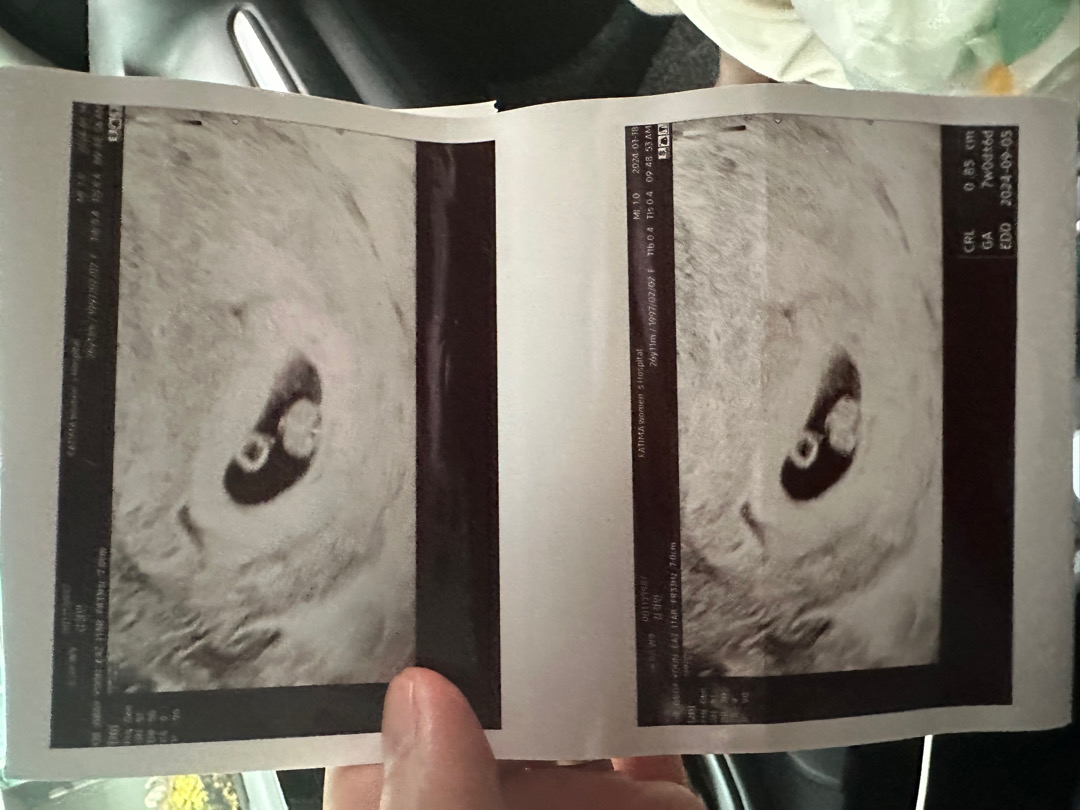

7주 0일

저번주이 갔을 땐 아기가 없었는데 오늘 진료보니까 아기가 나왔어용! 너무 귀여워요ㅜㅜ

우와 진짜 너무귀여워요 ㅠㅠㅠㅠㅠㅠ팔이 생긴건가요?? 대박 넘 귀엽다 ㅠㅠㅠㅠ